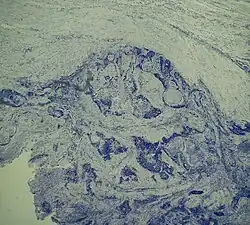

![]() Рак щитовидной железы. Илл. 1914 года | |